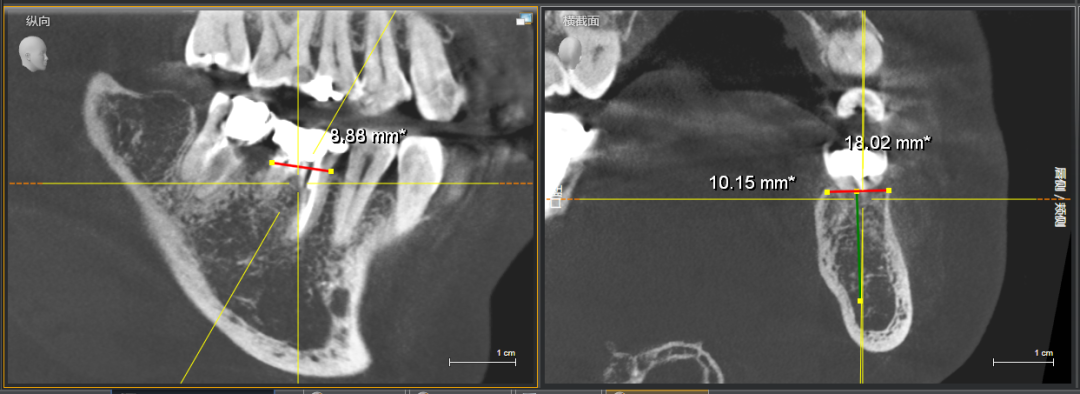

●46、47牙冠部见大面积银汞充填影像,充填物边缘影像见低密度影像,根管内见根充物影像(欠充),根尖未见低密度影像,牙槽骨宽度及高度条件良好

●采集CBCT数据和口内扫描,进行数字化设计